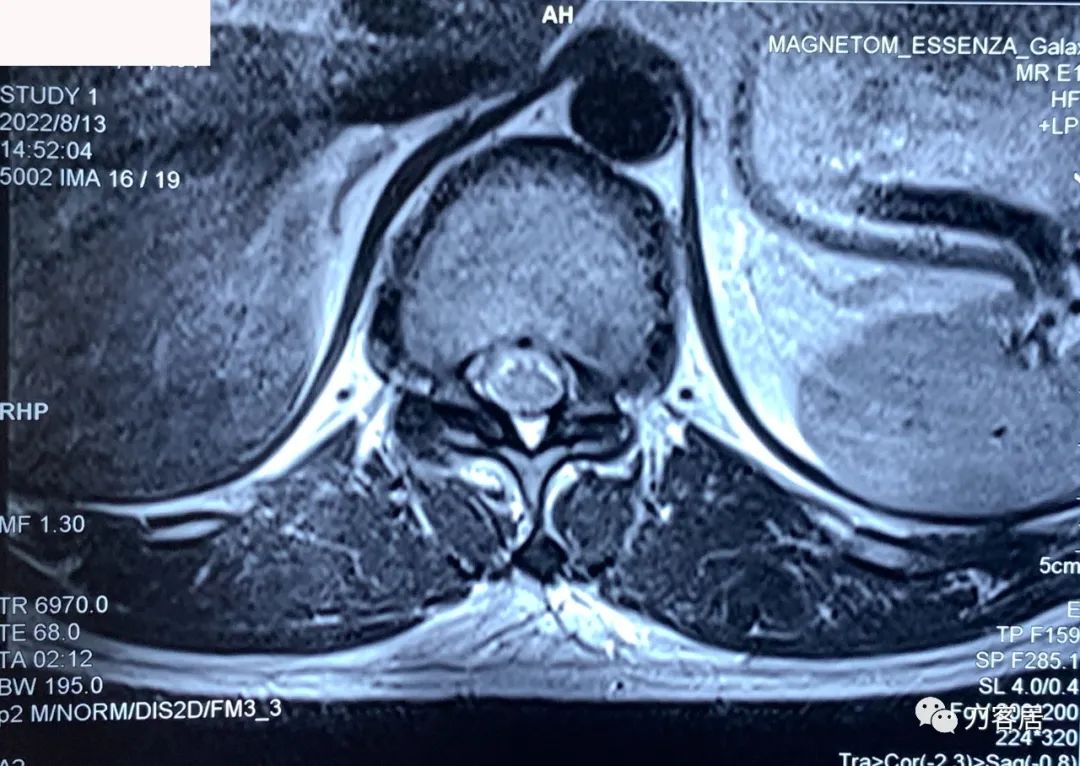

图7. 20220813西安第三方影像机构胸椎MRI01,提示胸8-9椎间盘突出,胸11-12椎间盘突出,椎管狭窄。

图8. 20220813西安第三方影像机构胸椎MRI02,提示胸8-9椎间盘突出,胸11-12椎间盘突出,椎管狭窄。

图10. 20220813西安第三方影像机构胸椎MRI04,提示右侧隐窝狭窄,右侧黄韧带肥厚,但椎管狭窄并不那么严重。

图11. 20220813西安第三方影像机构胸椎MRI05,显示两侧胸椎黄韧带肥厚,右侧明显。但脊髓压迫似乎并不那么严重。

图12. 20220813西安第三方影像机构胸椎MRI06,显示两侧胸椎黄韧带肥厚,右侧明显。但脊髓压迫似乎并不那么严重。